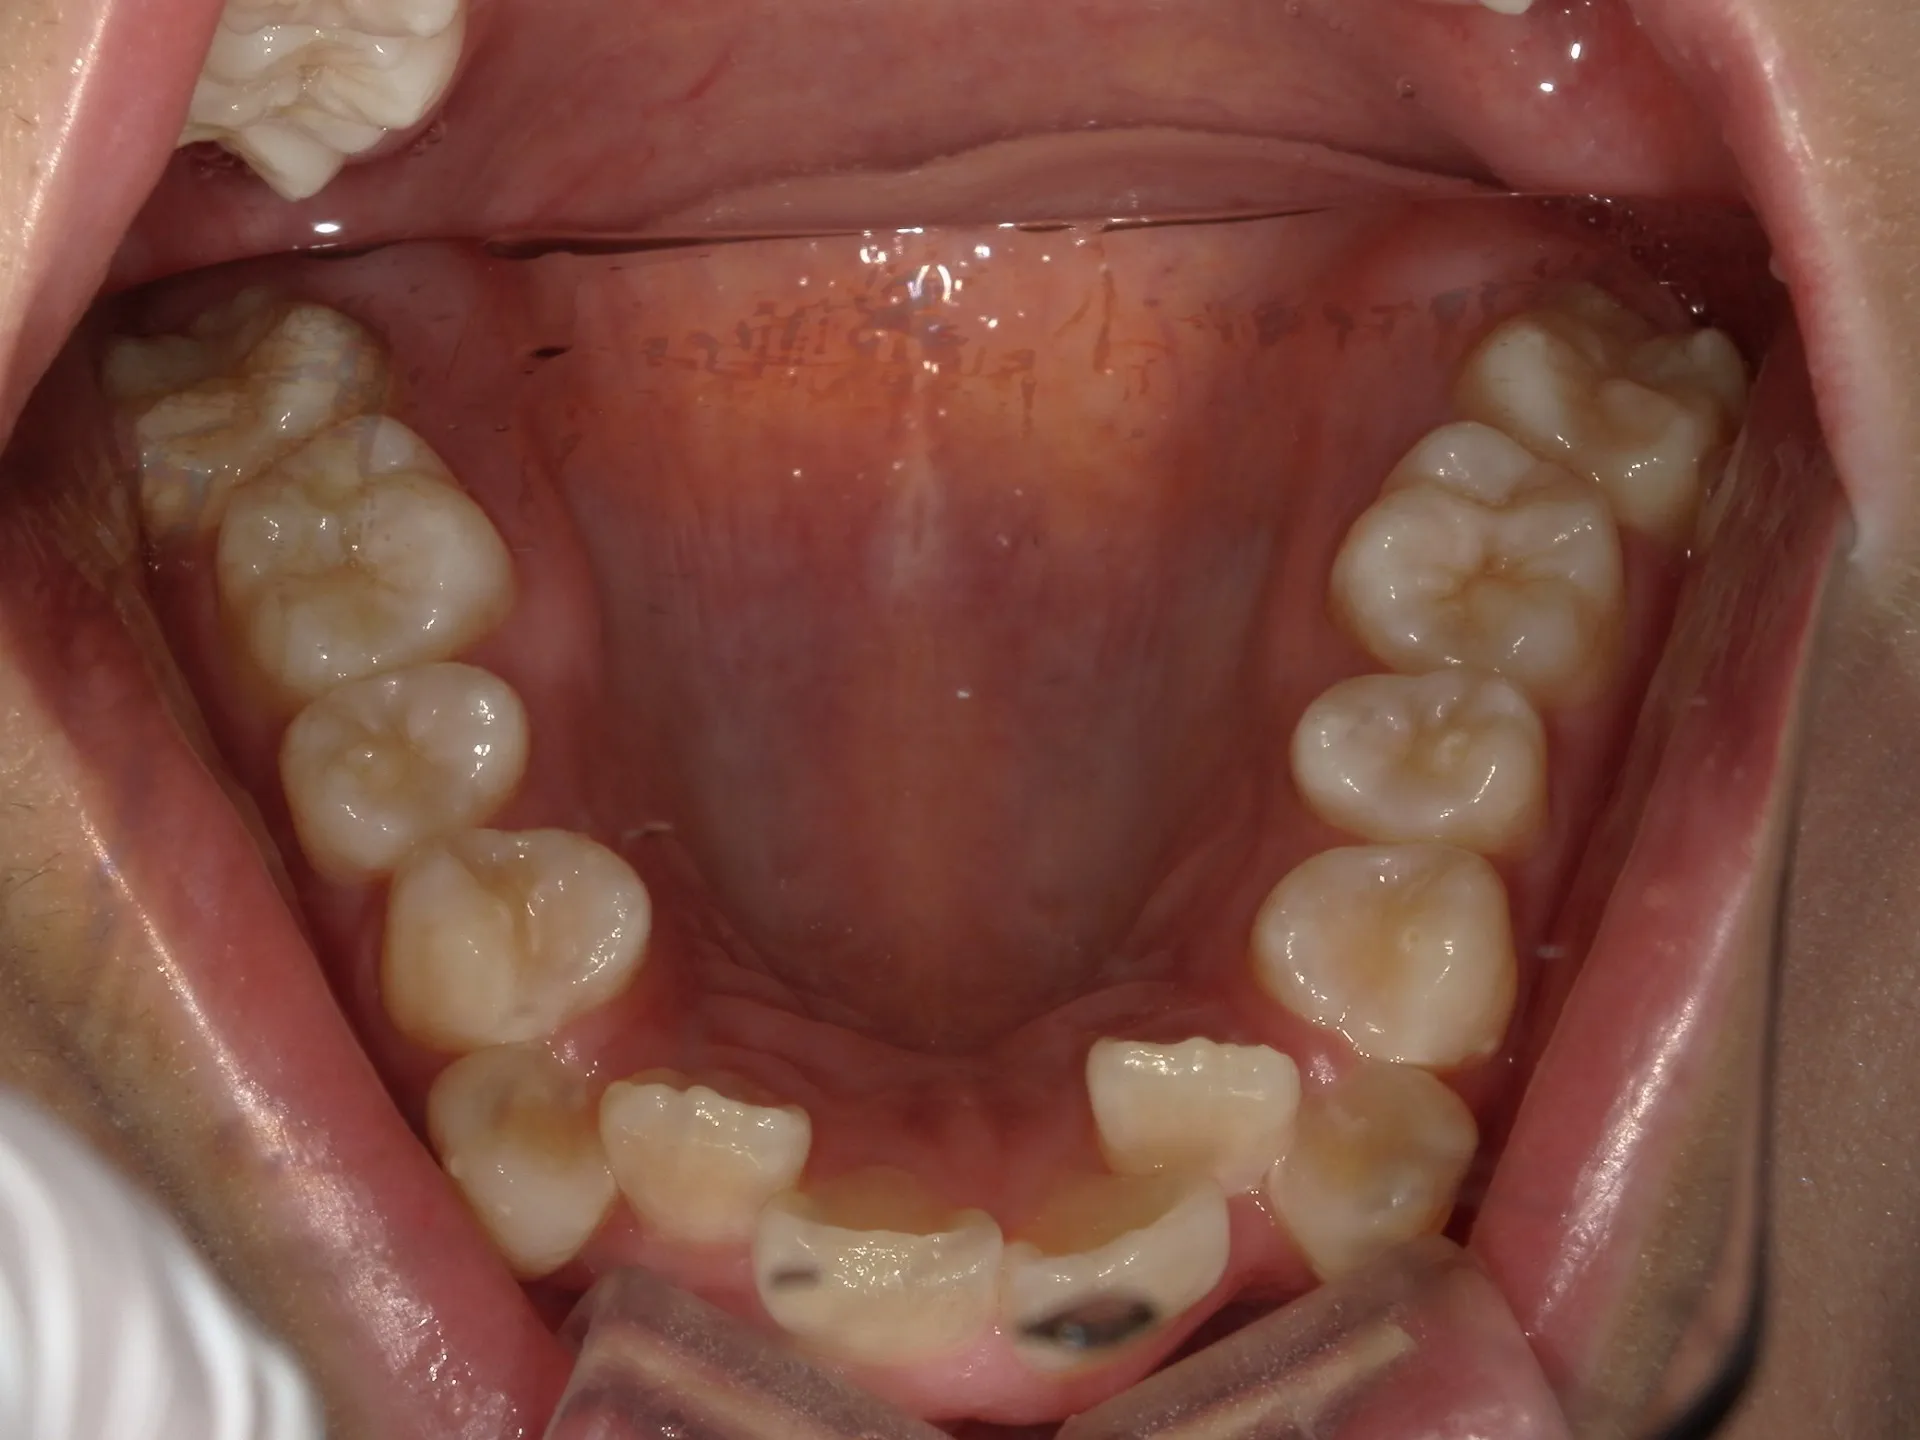

今回はマウスピース矯正で治療した八重歯の矯正についてご紹介いたします。

どこまでが軽度でどこまでが中等度のガタツキなのかにもよりますが、治療前の歯並びであれば患者さんの協力も当然必要ですが、マウスピース矯正でも十分治療できることが分かります。